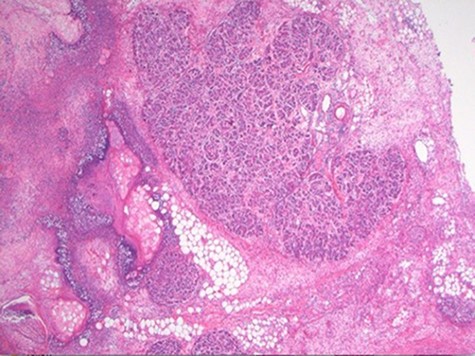

At laparoscopy, there were very dilated and inflamed loops of small bowel, and the appendix appeared normal macroscopically. Due to the extent of bowel dilatation obscuring adequate laparoscopic vision and assessment, decision was made to convert to an open procedure. At laparotomy, there was a nodular mass in the jejunal mesentery measuring about 3 cm in diameter with central necrotic tissue (Fig. 1). As it was adherent to the surrounding bowel, a limited small bowel resection was performed (Fig. 2) with side to side stapled anastomosis. Histology revealed normal small bowel wall with a mesenteric nodular mass comprised of architecturally normal pancreatic tissue including exocrine ducts and endocrine islets of Langerhans (Figs 3–5), consistent with a diagnosis of mesenteric heterotopic pancreas. His post-surgical recovery was uneventful and was discharged after five days of stay in hospital. He had an outpatient magnetic resonance imaging (MRI) of the pancreas which reviewed normal pancreas tissue, and he was followed up three months post-surgery.

Intraoperative finding of an inflammatory mass in the mesentery of jejunum with necrotic centre.